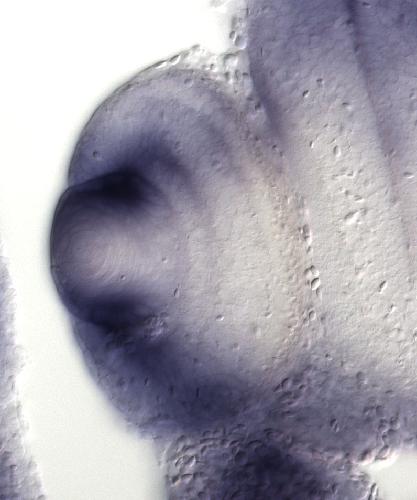

dhx38

DEAH-box helicase 38

mRNsplicing factor ATP-dependent RNA helicase

The gene dhx38 encodes an RNA helicase involved in pre-mRNA splicing as a component of the spliceosome complex. Its expression is detected in neural tissues including the developing eye, brain, and spi...[+]

retinitis pigmentosa